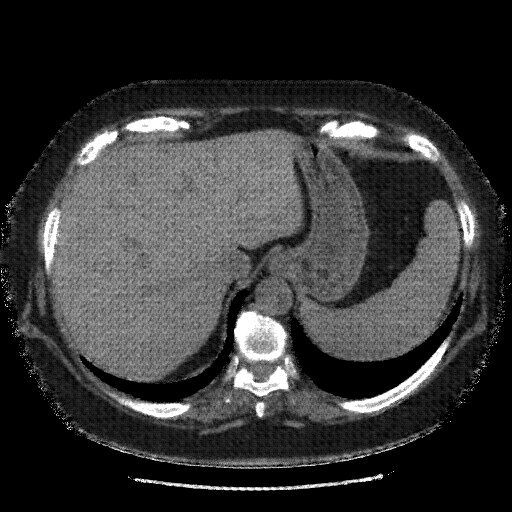

Original VENOUS CT scan

Full window (WL 1023.5, WW 4095 β†’ Low βˆ’1024, High +3071)

Actual HU range: [-1024.0, 1086.0]

Lung window (WL -600, WW 1500 β†’ Low βˆ’1350, High +150)

Actual HU range: [-1350.0, 150.0]

Mediastinum window (WL 40, WW 400 β†’ Low βˆ’160, High +240)

Actual HU range: [-160.0, 240.0]